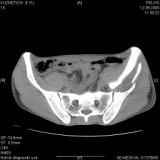

Уважаемые коллеги! Хотелось бы услышать совет по тактике лечения представлленого больного.Поступил после лечения в одном изотделений области. Травма 2,5 месяца назад. После выведенияиз шока был произведен остеосинтез перелома бедра, предплечья, до перевода к нам проводилосьвытяжение по оси шейки бедра за стержень, введенный в большой вертел. На сегодня деформацияригидна, клинически мобильности не определяется. Заранее признателен. P.S. Данный вид травм не включен в перечень "высокотехнологичных операций", направить длялечения по квотам Минздрава очень сложно.

Привет, Леонид. Оскольчатый высокий двухколонный перелом в такие сроки трогать не надо, т.к. это про такие переломы сказано: "кто с ножом на Ж. пойдет тот в ней и останется...".